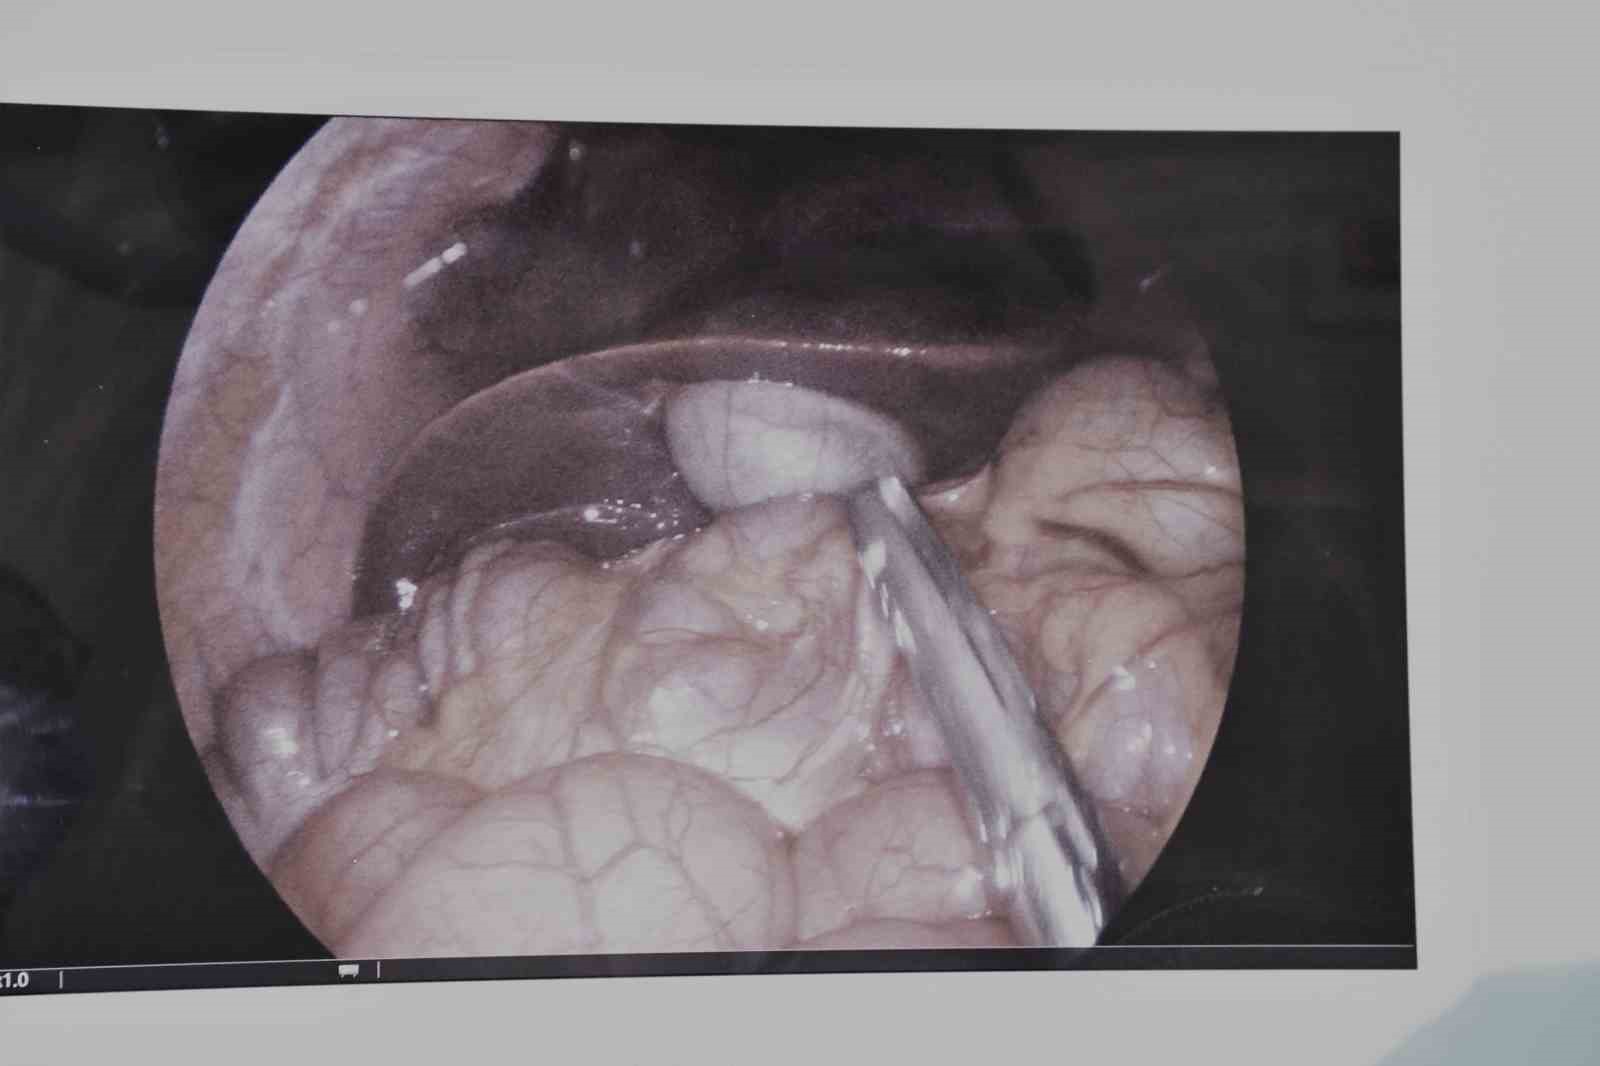

Sık sık tekrarlayan safra kesesi iltihaplanması (kolesistit) şikayeti bulunan 17 yaşındaki bir hasta, hastanede çocuk yaş grubunda ilk kez gerçekleştirilen laparoskopik kolesistektomi ameliyatı ile sağlığına kavuştu.

Operasyonu gerçekleştiren Çocuk Cerrahisi Uzmanı Op. Dr. Serkan Odabaşı, yaptığı açıklamada, hastanın uzun süredir karın ağrısı, mide bulantısı ve sindirim problemleri şikayetleri olduğunu belirtti. Dr. Odabaşı, yapılan detaylı tetkikler sonucunda safra kesesinde enfeksiyon tespit edildiğini ifade ederken, "Bu durumda en uygun tedavi yöntemi, safra kesesinin alınması yani kolesistektomi ameliyatıdır. Operasyonu kapalı (laparoskopik) yöntemle gerçekleştirdik. Laparoskopik cerrahi, karında büyük kesiler açmadan, küçük delikler aracılığıyla özel cerrahi aletlerle yapılan modern bir tekniktir. Bu sayede hastamızın ameliyatı başarılı bir şekilde tamamlandı. Hastamızın kısa sürede taburcu edilmesi planlanmaktadır” dedi.